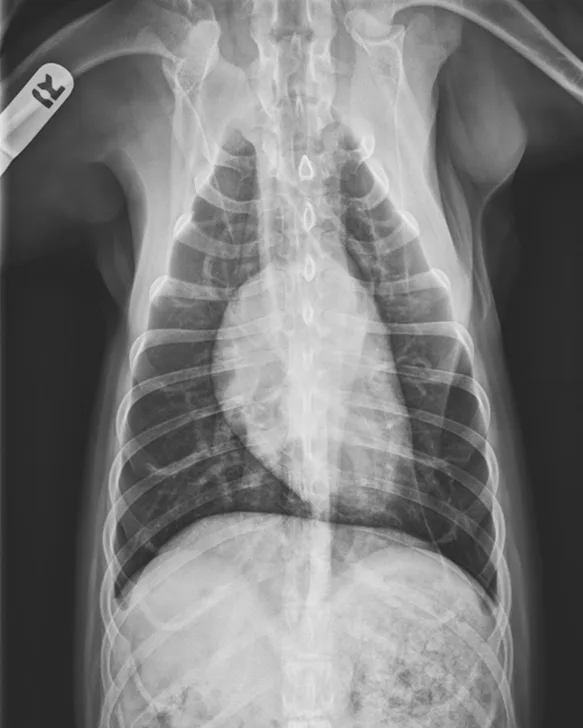

Thoracic radiographs showing a characteristic diffuse, patchy bronchointerstitial pattern (arrows)

Thoracic radiographs revealed a moderate, diffuse, bronchointerstitial pattern (Figure 1). The cardiac silhouette, pulmonary vasculature, and extrathoracic structures were normal. Airway sampling via bronchoscopy was recommended based on radiographic findings. CBC and serum chemistry profile were performed prior to sedation. Serum chemistry results were within normal limits. CBC revealed leukocytosis (24.3 x 103/µL; normal range, 4.9-17.6 x 103/µL) characterized by marked eosinophilia (10.4 x 103/µL; normal range, 0.07-1.49 x 103/µL), monocytosis (1.4 x 103/µL; normal range, 0.13-1.15 x 103/µL), and band neutrophilia (729/µL; normal range, 0-170/µL). Heartworm antigen test was negative.

Thoracic radiographs are generally characterized by a diffuse bronchointerstitial pattern with peribronchial cuffing and thickening of the bronchial walls. In some cases, bronchiectasis or alveolar infiltration may be observed.2,6-8 Occasionally, patchy pulmonary opacities create a nodular appearance.4 Radiography is critical for ruling out other common causes of cough and/or acute respiratory distress. Concurrent disease processes (eg, cardiomegaly, tracheal collapse) can complicate diagnosis.